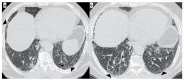

Background: Idiopathic pulmonary fibrosis (IPF) is a progressive fibrosing interstitial lung disease (ILD). This prospective observational study aimed at the evaluation of any correlation between genetic variants associated with IPF susceptibility and high-resolution computed tomography (HRCT) patterns. It also aimed at evidencing any differences in the HRTC pattern between the familial and sporadic form at diagnosis and after two years.

Results: A total of 19 familial (mean age 62 ± 15) and 46 sporadic (mean age 70 ± 9) IPF patients were enrolled. A statistically significant difference was evidenced in the HRTC pattern at diagnosis between the two groups. Sporadic IPF patients had a predominantly usual interstitial pneumonia (UIP) pattern compared with those patients with familial IPF (60.0% vs. 21.1%, respectively). Moreover, familial IPF patients had more alternative diagnoses than those with sporadic IPF (31.6% vs. 2.2%, respectively). Furthermore, there was a slight increase in the typical UIP pattern in the familial IPF group at two years from diagnosis.